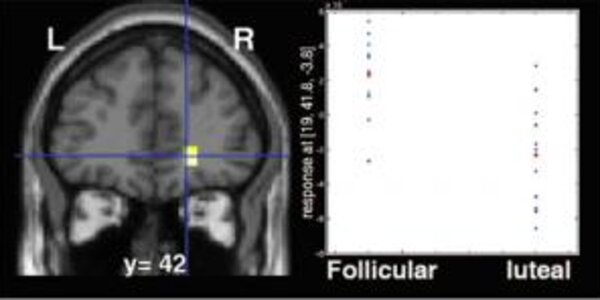

Fluctuations in sex hormone levels during women's menstrual cycles affect the responsiveness of their brains' reward circuitry, an imaging study at the National Institute of Mental Health (NIMH), a component of the National Institutes of Health (NIH), has revealed. While women were winning rewards, their circuitry was more active if they were in a menstrual phase preceding ovulation and dominated by estrogen, compared to a phase when estrogen and progesterone are present. Brain activity in the orbitofrontal cortex (yellow), part of the brain's reward system, was increased during women's pre…

What influence does the variation in estrogen level have on the activation of the female brain? Using functional Magnetic Resonance Imaging, Jean-Claude Dreher, a researcher at the Cognitive Neuroscience Center (CNRS/Université Lyon 1), in collaboration with an American team from the National Institute of Mental Health (Bethesda, Maryland) directed by Karen Berman, has identified, for the first time, the neural networks involved in processing reward-related functions modulated by female gonadal steroid hormones. This result, which was published online on January 29, 2007 on the PNAS website…